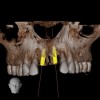

For dental implant-based treatment, the planning phase begins with collection of basic data sets; this is digital touchpoint 1. It includes: (1) a cone-beam CT (CBCT) to view edentulous areas or failing tooth structure, bone, and anatomic landmarks under the soft tissue (Figure 2 through Figure 4); and (2) an intraoral optical scan (IOS) or a scanned model or impression to record the soft tissue and tooth anatomy (Figure 5). The superimposition of the digital imaging and communications in medicine (DICOM) files from the CBCT and the standard tessellation language (STL) files from the IOS allows visualization of how bone, dental structures, and soft tissues relate. Both digital data points are key to implant selection and determining the surrounding bone-grafting needs. An initial treatment plan includes determining the desired implant manufacturer/implant design, size, and positions; these decisions remain the responsibility of the clinician (restoring and surgical team members) and not the technician or planning team.

To reduce the time and costs associated with the steps required to use these digital data sets, DICOM and STL files may be outsourced for off-site data management and virtual restoration design; this is referred to as digital touchpoint 2. This may be carried out by clinicians involved in the case if they are so inclined, or by a planning team, whether it be a laboratory or other service center. Using a trained planning team can significantly accelerate the preparation process.

4. The entire set-up allows a preview of hard/soft-tissue augmentation or reduction requirements based on virtual and desired implant positions. It is here that decisions are made as to whether the plan can be achieved, or if pre-prosthetic steps such as orthodontic and orthognathic procedures are necessary to avoid open bites or reverse smiles. The benefit in virtually previewing the lip position relative to the transition zone (tissue-prosthesis interface) may especially be appreciated in all-on-4 or -6 full-arch implant restorations. Bone reduction guides or planned implant positions relative to a "virtually" reduced ridge to allow apical correction of the tissue-prosthesis interface are critical to the esthetic success of a prosthesis. "Face-in" planning literally eliminates this challenge (Figure 10 and Figure 11).